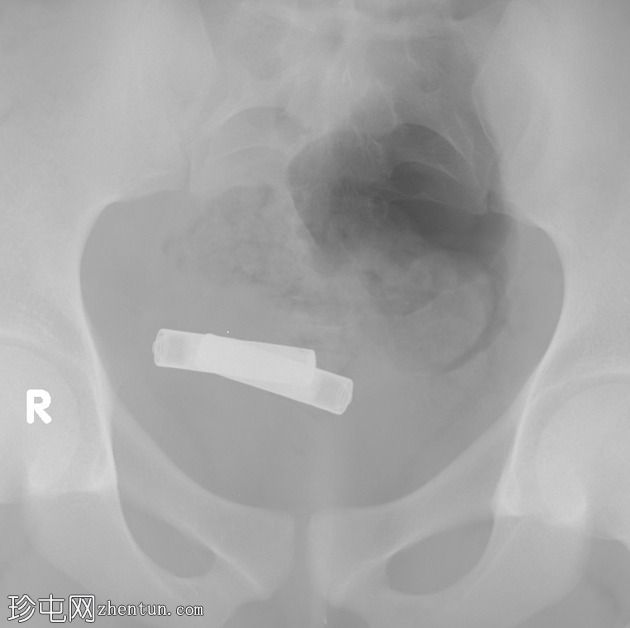

X线片

正位片

盆腔内可见两个不透射线的异物。